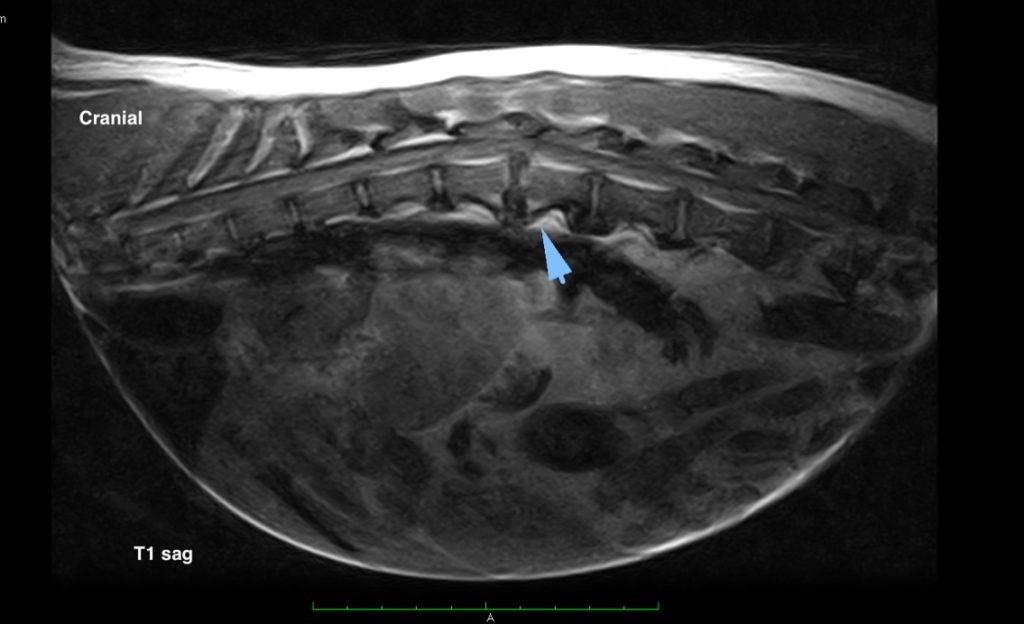

Advanced imaging with computer tomography (CT) or Magnetic Resonance Imaging (MRI) as well as hospital facilities would be required for these cases

Advanced imaging with computer tomography (CT) or Magnetic Resonance Imaging (MRI) as well as hospital facilities would be required for these cases